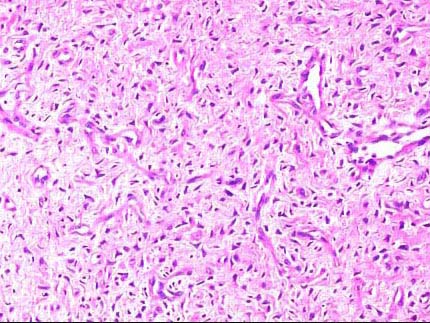

患者,男,18岁,鼻塞、鼻出血,鼻腔镜检查见一鲜红色圆形肿物凸向鼻腔,约2cm×1cm×0.5cm大小,表面光滑,活检如图1、2所示,正确的诊断是 ( )

• E.鼻腔纤维血管瘤